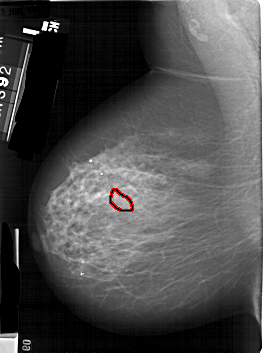

FILE: A_1824_1.LEFT_MLO.OVERLAY

TOTAL_ABNORMALITIES 1

ABNORMALITY 1

LESION_TYPE CALCIFICATION TYPE PLEOMORPHIC DISTRIBUTION SEGMENTAL

ASSESSMENT 4

SUBTLETY 3

PATHOLOGY MALIGNANT

TOTAL_OUTLINES 1

BOUNDARY